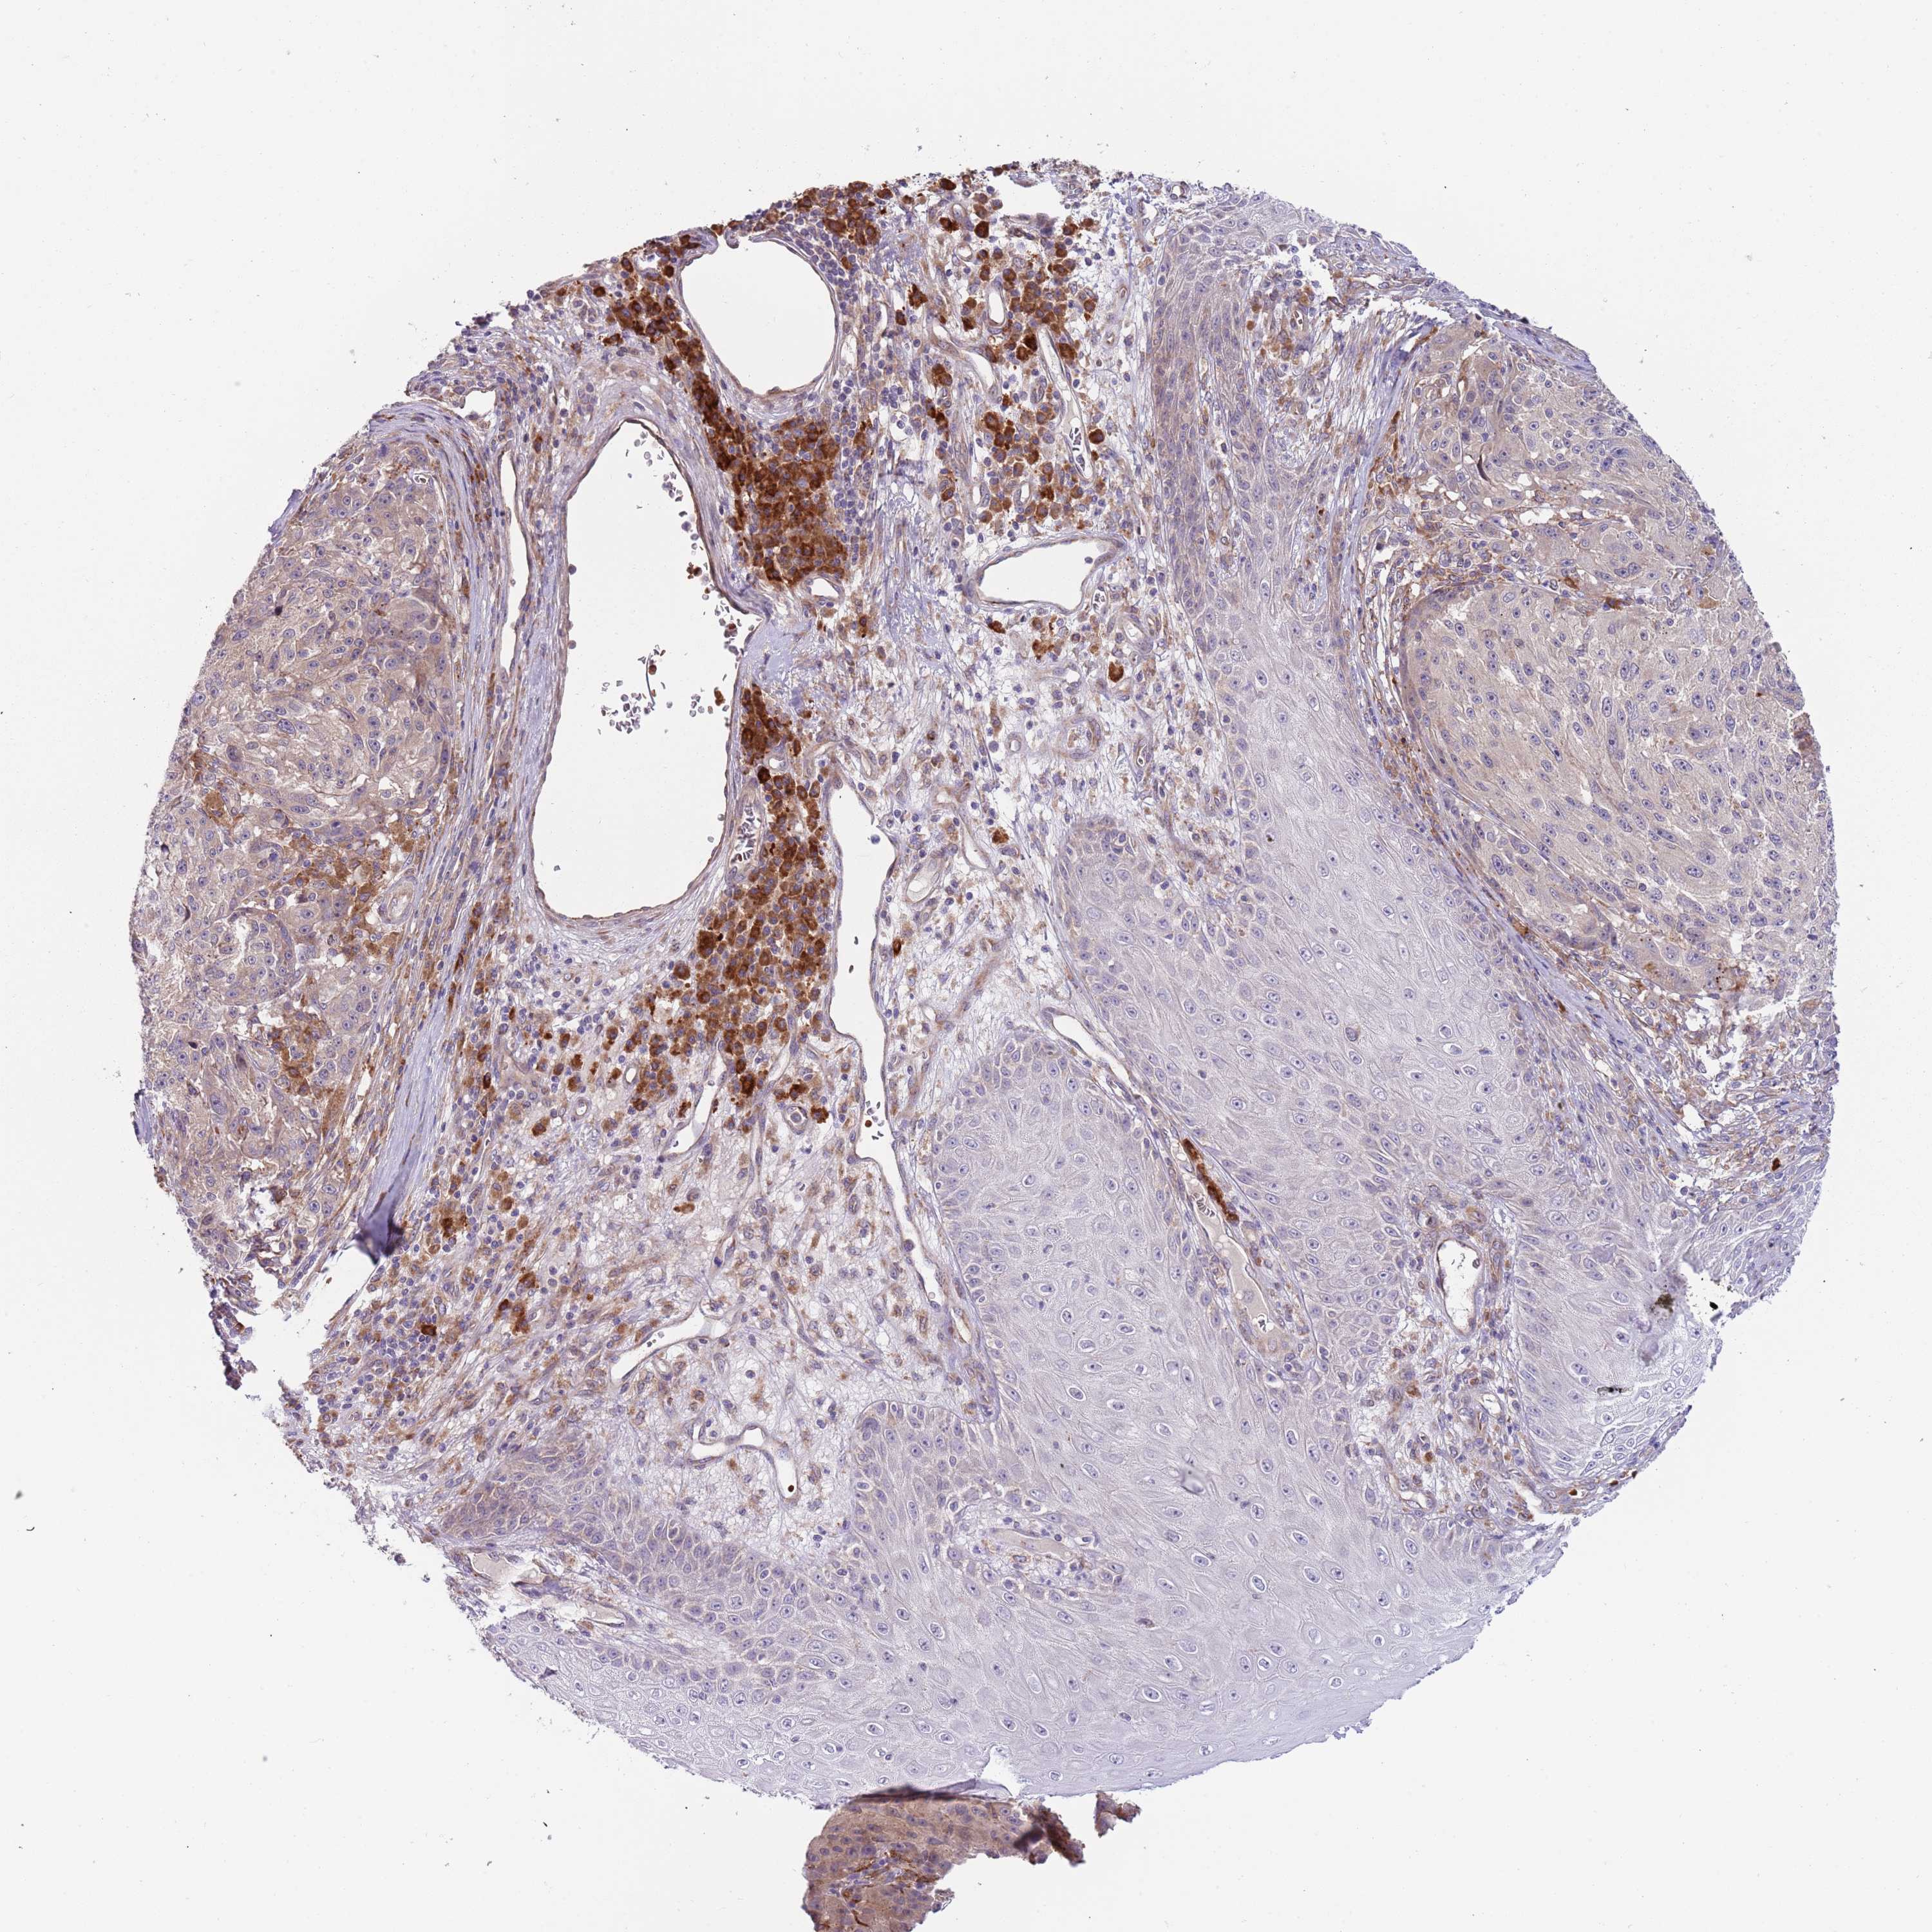

MELANOMA - Protein expressioni

A mouse-over function shows sample information and annotation data. Click on an image to view it in a full screen mode. Samples can be filtered based on level of antibody staining by selecting one or several of the following categories: high, medium, low and not detected. The assay and annotation is described here.

Note that samples used for immunohistochemistry by the Human Protein Atlas do not correspond to samples in the TCGA dataset.

Antibody stainingi

Antibody staining in the annotated cell types in the current human tissue is reported as not detected, low, medium, or high, based on conventional immunohistochemistry profiling in selected tissues. This score is based on the combination of the staining intensity and fraction of stained cells.

Each image is clickable and will lead to virtual microscopy that enables deeper exploration of all samples and also displays staining intensity scores, fraction scores and subcellular localization as well as patient and tissue information for each sample.

Antibody HPA040401

Antibody HPA043921

Staining

High

Medium

Low

Not detected

Intensity

Strong

Moderate

Weak

Negative

Quantity

>75%

75%-25%

<25%

None

Location

Nuclear

Cytoplasmic/membranous

Cytoplasmic/membranous,nuclear

Malignant melanoma, NOS

Malignant melanoma, Metastatic site